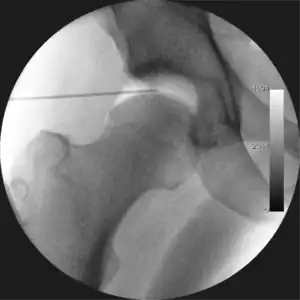

Figure 4. A needle is passed into the joint, breaking the 'suction seal', and allowing further distraction of the hip joint with minimal extra traction

The next step is to insert a fine needle under x-ray guidance into the hip joint. This breaks the 'suction seal' of the joint and allows further distraction if necessary (see fig 4). The surgeon wishes to see the ball move out the socket by approximately 1 cm, so that access to the hip joint can be achieved with minimal risk of damage to the joint surfaces. Most surgeons will inject fluid into the joint at this stage, again to ensure that there is enough space between the ball and socket for safe instrument access. This needle is then removed. The next step is placement of the 'portals', or the small holes made to pass instruments into the joint. This is achieved by again passing a fresh hollow needle into the joint under x-ray control, usually in a slightly different position. The reason for this is so the surgeon can ensure that the needle, and subsequent cannulae do not penetrate and damage the acetabular labrum or cartilage joint surfaces (see fig. 5). Again, surgeons will have their own preferences as to their preferred placement. Through this hollow needle, a long thin flexible guide wire is passed into the joint, and the needle is removed over it, leaving the guide wire in situ. A small cut in the skin is made around the wire, to allow for larger cannulae to be placed over the wire through the portal. The wire therefore guides the larger cannulae into the joint. The most common external diameters of cannulae used are between 4.5 and 5.5 mm. Once the surgeon is satisfied that the cannula is in the correct position, by a combination of feel and x-ray guidance, the guide wire can be withdrawn. Once the first portal is correctly placed, any further portals may be created once the camera is in position, to ensure that they are placed with minimal risk to the joint surfaces. This process can be repeated to gain as many points of entry to the hip joint as the surgeon requires, normally between two and four. Certain of these entry points will be used for the viewing arthroscope and others for operating instruments.